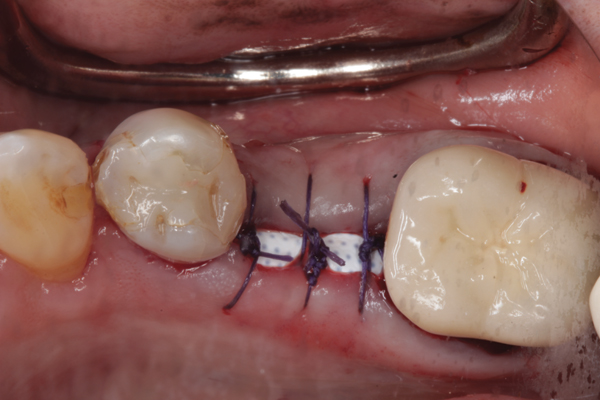

Fig 6. d-PTFE barrier in position, and the flap sutured.

Figure 6